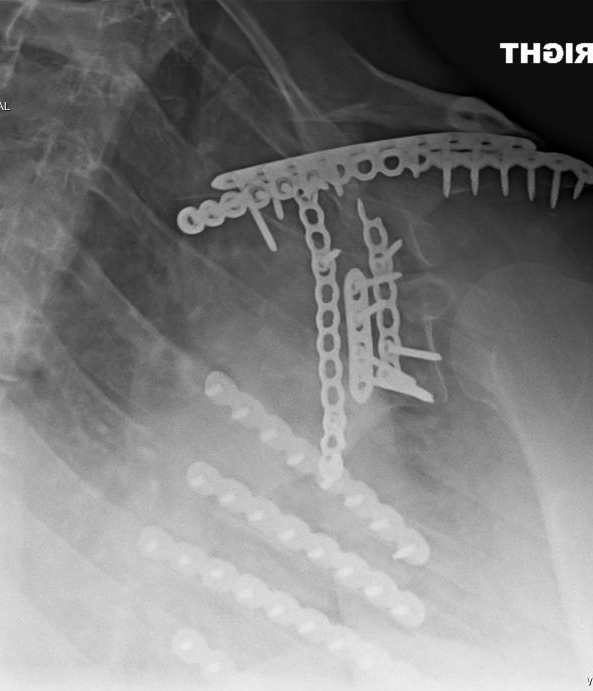

Today marks a milestone in the life of myself and my family. Today is the 11th-year survivor-versary of the wreck that, in part, changed the course of all of our lives.

While it remains factual that it was myself and our youngest son involved in the actual wreck itself all those years ago, the family as a whole would become and remain affected as a result of its aftermath – for years to come.  The rehabilitation journey has not been for the faint of heart and continues…albeit in different ways now than when it all began.